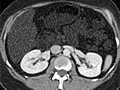

A computed tomography (CT) scan uses X-rays to make detailed pictures of structures inside of the body.

A CT scan can be used to study all parts of your body, such as the chest, belly, pelvis, or an arm or leg. It can take pictures of body organs, such as the liver, pancreas, intestines, kidneys, bladder, adrenal glands, lungs, and heart. It also can study blood vessels, bones, and the spinal cord.